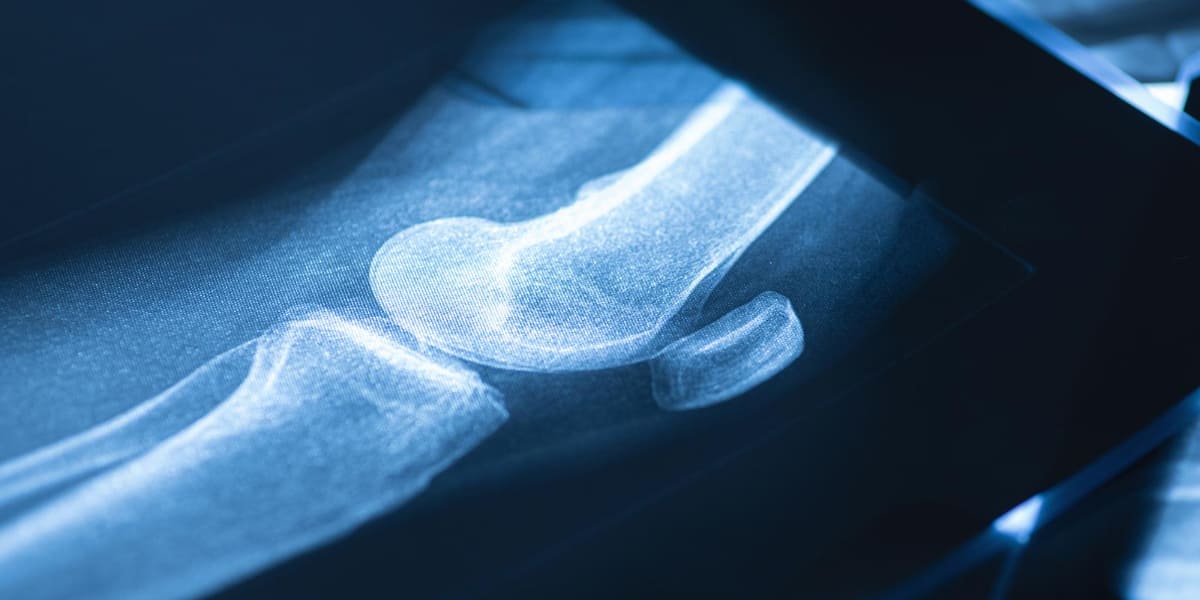

Nah, kalau kamu penasaran bagaimana bentuk tulang paha sebenarnya, kamu datang ke artikel yang tepat. Tulang paha manusia berbentuk tulang pipa, yakni tulang panjang yang bentuknya mirip seperti pipa.

Bagian atas dan bawah tulang paha memiliki ujung yang menyambung dengan tulang lain untuk membentuk persendian. Tulang ini memiliki rongga atau lubang spion kecil di tengahnya. Ini disebut sumsum tulang kuning dan merah.

Sumsum tulang berperan penting dalam produksi sel darah dalam tubuh. Struktur dari tulang ini keras dan juga padat, sehingga berfungsi sebagai penopang berat badan dan juga sebagai tumpuan pergerakan tubuh kita.